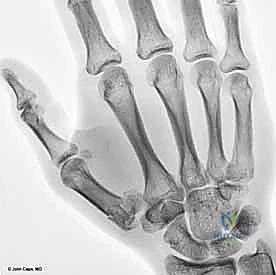

يتكون هذا المفصل من التقاء قاعدة عظم المشط الأول للإبهام (First Metacarpal Bone) مع العظم المربعي (Trapezium) الموجود في صف عظام الرسغ. يُصنف هذا المفصل من الناحية التشريحية على أنه "مفصل سرجي حقيقي" (Saddle Joint). هذا يعني أن الأسطح المفصلية لكلا العظمين تتخذ شكلاً مقعراً في اتجاه ومحدباً في الاتجاه الآخر، مما يسمح لها بالتشابك التام.

1. كسر بينيت (Bennett's Fracture)

هو أشهر أنواع كسور قاعدة الإبهام وأكثرها تعقيداً. وهو كسر داخل المفصل يتميز بوجود خط كسر مائل يفصل شظية صغيرة من الجانب الراحي الزندي (Volar-Ulnar) لقاعدة المشط الأول.

* الديناميكا المرضية: المشكلة الكبرى في كسر بينيت هي "القوى العضلية المعاكسة". بينما تظل الشظية الصغيرة ثابتة في مكانها بفضل رباط المنقار القوي، تقوم عضلة "مبعدة الإبهام الطويلة" (Abductor Pollicis Longus - APL) بسحب الجزء الأكبر المتبقي من عظم المشط إلى الأعلى والخلف، مما يؤدي إلى خلع جزئي (Subluxation) للمفصل.

* هذا الكسر غير مستقر بطبيعته ويحتاج دائماً إلى تدخل لتثبيته.